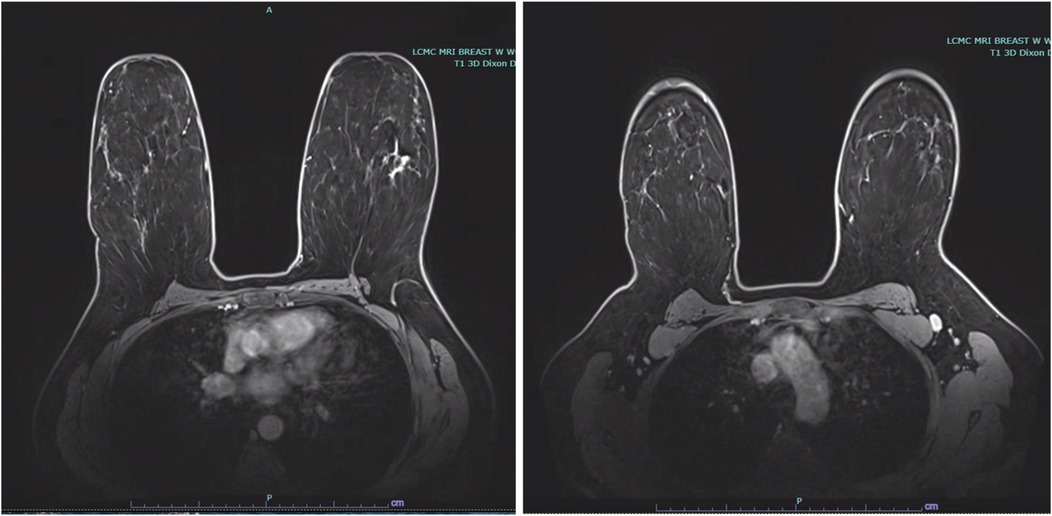

Stereotactic core needle biopsy completed 2 weeks later, confirmed high-grade DCIS with solid pattern, focal minimal comedonecrosis, and focal microcalcifications in the left breast. No lymphovascular invasion was identified. MRI correlated the non-palpable area of abnormality with a 5.2 cm area of non-mass enhancement. MRI also noted a prominent level 1 left axillary lymph node with no internal mammary lymphadenopathy (Figure 2).

Figure 2. Bilateral breast MRI depicting malignancy in the upper outer quadrant of the left breast with non-mass enhancement measuring 5.2 cm, in addition to a prominent level 1 left axillary lymph node.